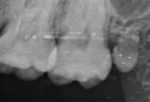

私は先日、ついに左上の過剰歯の抜歯をしてきました!!

左上の親知らずを抜いたのは学生の時だったので、もう6年はたちました。

その時にはかなり上にいた過剰歯が先月ついに萌出しました😂